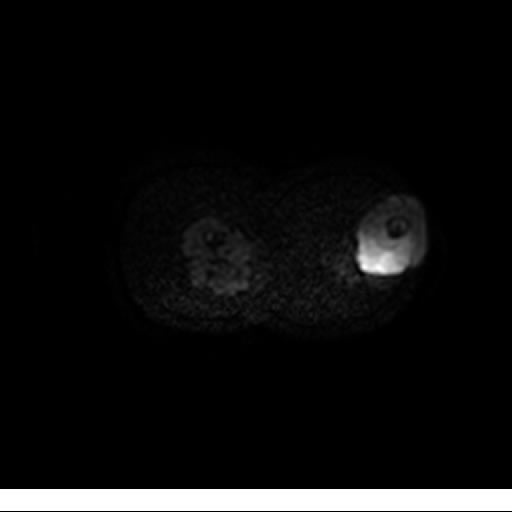

Se realiza estudio de MRI de muslo izquierdo en diferentes planos, con secuencias de Spin Echo, GRE; ponderadas a T1 y a T2, se utilizan pulsos de saturación de grasa y se administra medio de contraste IV a base de Gadolinio en base al peso del paciente.

La diáfisis femoral izquierda muestra reacción perióstica importante, se extiende desde el cuello del fémur, invade trocánteres, diáfisis femoral, medial y distal, es compatible con un proceso infeccioso óseo, el complejo muscular del muslo se ve edematizado.

Hallazgos en Resonancia Magnética (RM)

La resonancia es la modalidad de elección para valorar la extensión intramedular y la infiltración en tejidos blandos, brindando una imagen más detallada del compromiso tumoral. Los hallazgos característicos incluyen:

Lesión de señal heterogénea en secuencias T1 (hipointensa) y T2/STIR (hiperintensa), que refleja necrosis, hemorragia y contenido celular diverso.

Realce intenso y heterogéneo tras la administración de contraste (gadolino), lo que indica vascularización tumoral.

Compromiso de la médula ósea adyacente y de estructuras vecinas, como músculos y neurovasculatura.

Posible presencia de edema óseo y necrosis central.